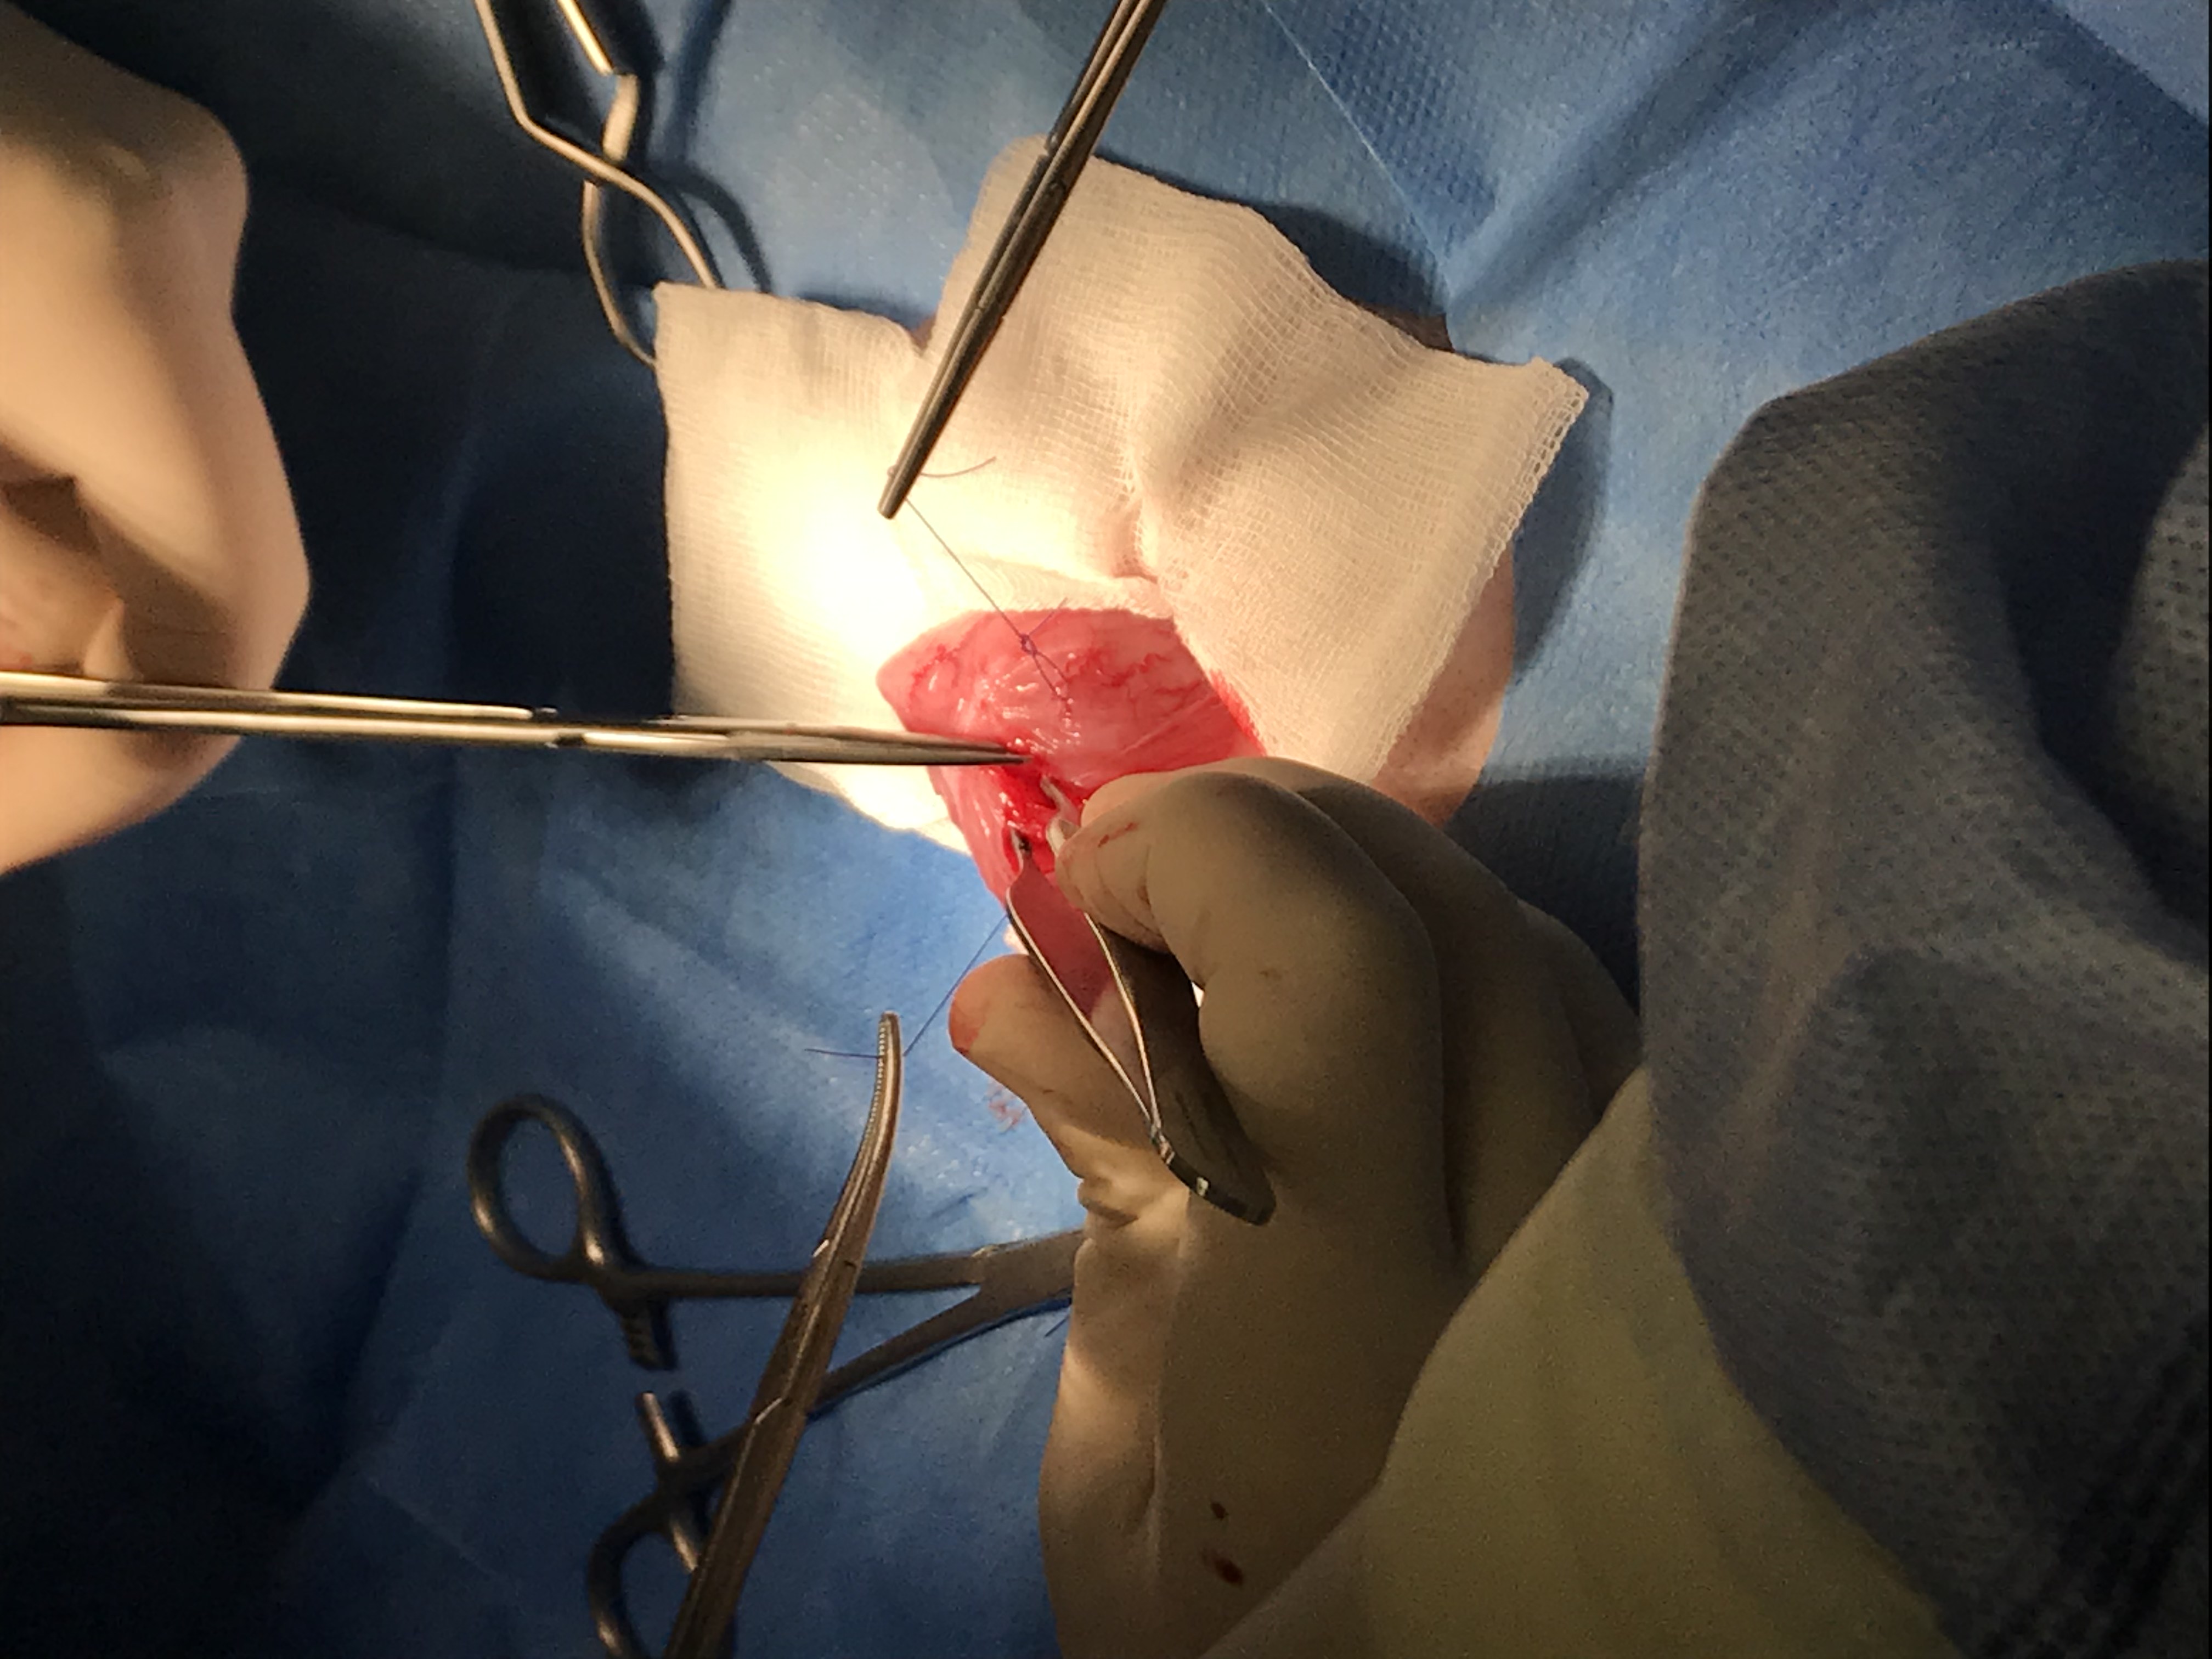

La cirugía transcurre perfectamente, se retiran todos los urolitos de la vejiga, los cuales, deberán ser enviadas a laboratorio externo, para de esta manera saber que tipo de composición tiene y poder poner una dieta acorde para prevenir la reaparición de las mismas.